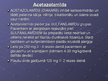

Diurētiskie līdzekļi

Diurētiskie līdzekļi

Diurētiskie līdzekļi